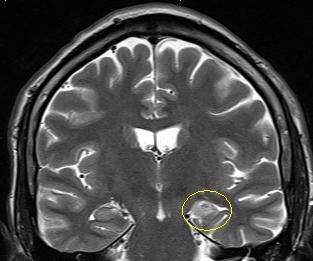

Es handelt sich um ein bildgebendes Verfahren, bei dem die Patienten in einer Röhre liegen und währenddessen mit Hilfe von wechselnden Magnetfeldern nach einem speziellen Epilepsie-Protokoll Bilder des Gehirns gemacht werden. So können Tumoren, Fehlbildungen oder andere Veränderungen des Gehirns, die Anfälle verursachen können, sichtbar gemacht werden. Durch moderne computergesteuerte Nachbearbeitungsmethoden oder Überlagerung mit anderen Bildmodalitäten können Läsionen dann noch besser dargestellt werden.

Folgende Veränderungen oder Erkrankungen des Gehirns werden häufig und mit gutem Erfolg (70-80% Anfallsfreiheit) epilepsiechirurgisch behandelt:

Hippocampussklerose

Fokale

cortikale Dysplasie